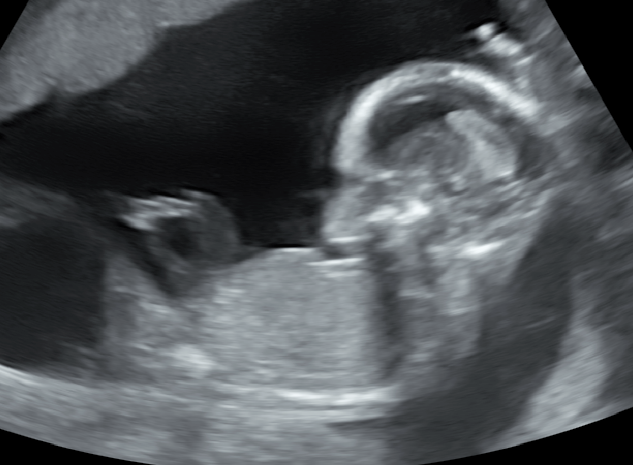

미성숙난자채취 시험관아기시술 후 졸업

7-8년전부터 생리불순이 있어 2020년부터 난임치료를 시작했던 30대 중반의 환자분입니다. 난임검사 상 양...